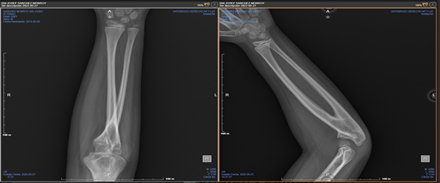

On physical examination, the right upper limb was normal. The left upper limb exhibited complete elbow flexion with extension limited to –10°, wrist pronation of 70°, and supination of –20°. Given these findings, plain anteroposterior and lateral radiographs of the left elbow were obtained, confirming the diagnosis of radioulnar synostosis (Figure 1). According to the Cleary and Omer classification, the synostosis was grade III (severe). The patient scored 6 points on the Failla functional scale, indicating severe impairment. Based on these assessments, we decided to proceed with surgical resection of the synostosis via a posterior approach.

Figure 1 Preoperative anteroposterior and lateral radiographs of the right forearm.

Caption: Radiographs showing proximal radioulnar synostosis before surgical intervention.